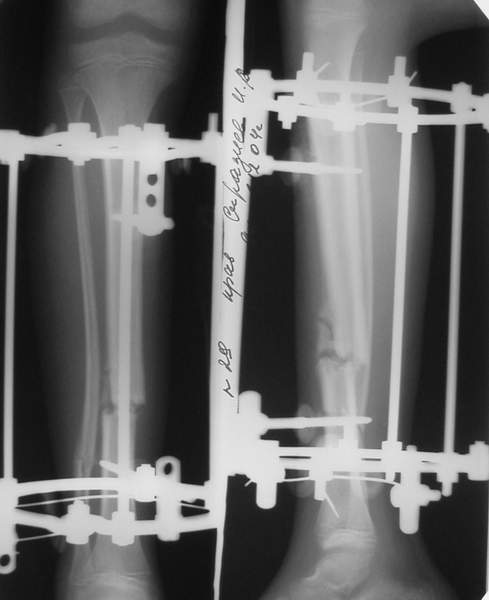

3b

3c

PS.

В аттачте № 3 - один из примеров полукольцевого аппарат...

Это уже я баловался.

Итог? Работы больше (по времени и

интраоп "подгонке"), срастается также, а особого преимущества по сравнению с

"чиста" кольцевым (вес, удобство ношения и пр.) - я, по крайней мере,

не нашел.

Теперь не балуюсь.

Может быть зря?

;-)

МТ мы используем, конечно, не только на голени. В прилагаемом примере у парня при поступлении была наружная ротация 40 гр. и "полумертвый" коленный сустав. Можно был бы, конечно, до конца использовать полную компоновку. Но для того он и есть метод выбора.